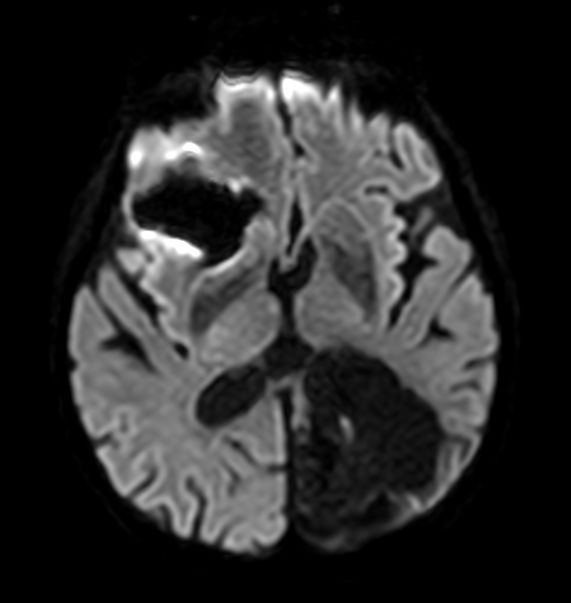

Axial Diffusion (b1000)

Axial Diffusion (ADC)